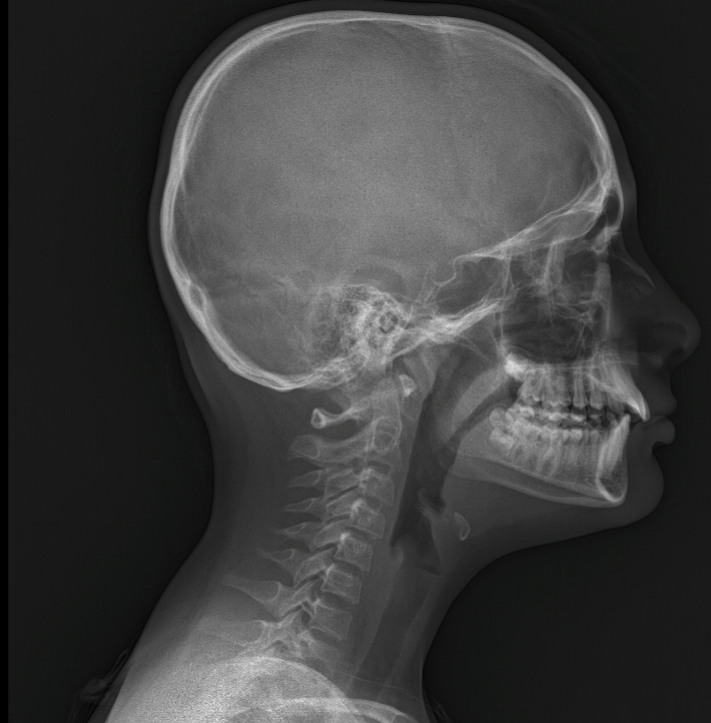

2019/2022 boyun düzleşmesi.

Diğeri de skolyoz derecesi nedir?

Boy uzamasında etkisi olur mu skolyozun?

Yaş 16.